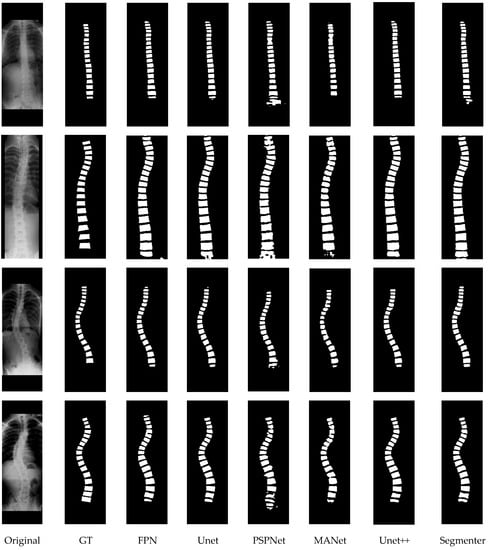

The quantitative experimental results of the compared methods are presented in Table 3, where ⊗ denotes that post-processing was not used for the segmentation results; √ denotes that post-processing was used; and + indicates the increase with the post processing used. To intuitively present the visual comparison, the segmentation effects of the different methods are shown in Figure 14, and some examples that illustrate the effects of post-processing are presented in Figure 15.

Figure 14.

The visual comparison of different segmentation networks. GT: ground truth.

First, as shown in Table 3, the Segmenter achieved the best results with accuracy (0.946), sensitivity (0.915), specificity (0.997), dice (0.915), and MIoU (0.848), while Unet++ achieved the second-best results with accuracy (0.940), sensitivity (0.743), specificity (0.983), dice (0.805), and MIoU (0.679). In general, the accuracy and specificity are relatively superior among these methods, but the sensitivity, dice, and MIoU could be improved. This illustrates that the segmentation network approach is limited in terms of dealing with the details of the segmented vertebrae. More intuitive examples can be found in Figure 14.

Second, by observing the visual comparison in Figure 14, various errors such speckles, adhesions, and redundances exist in the segmentation results for different methods. For example, PSPNet has more speckle errors, and MANet has more adhesion errors. However, Unet++ achieved the best subjective results, which are reflected in the clearer segmentation contour and less adhesion errors. Segmenter has more speckles and adhesions in the subjective presentation than Unet++, even though Segmenter achieves high quantitative evaluation values. This greatly affects the Lenke classification performance of scoliosis, which partly why we use Unet++ as the recommended segmentation network.